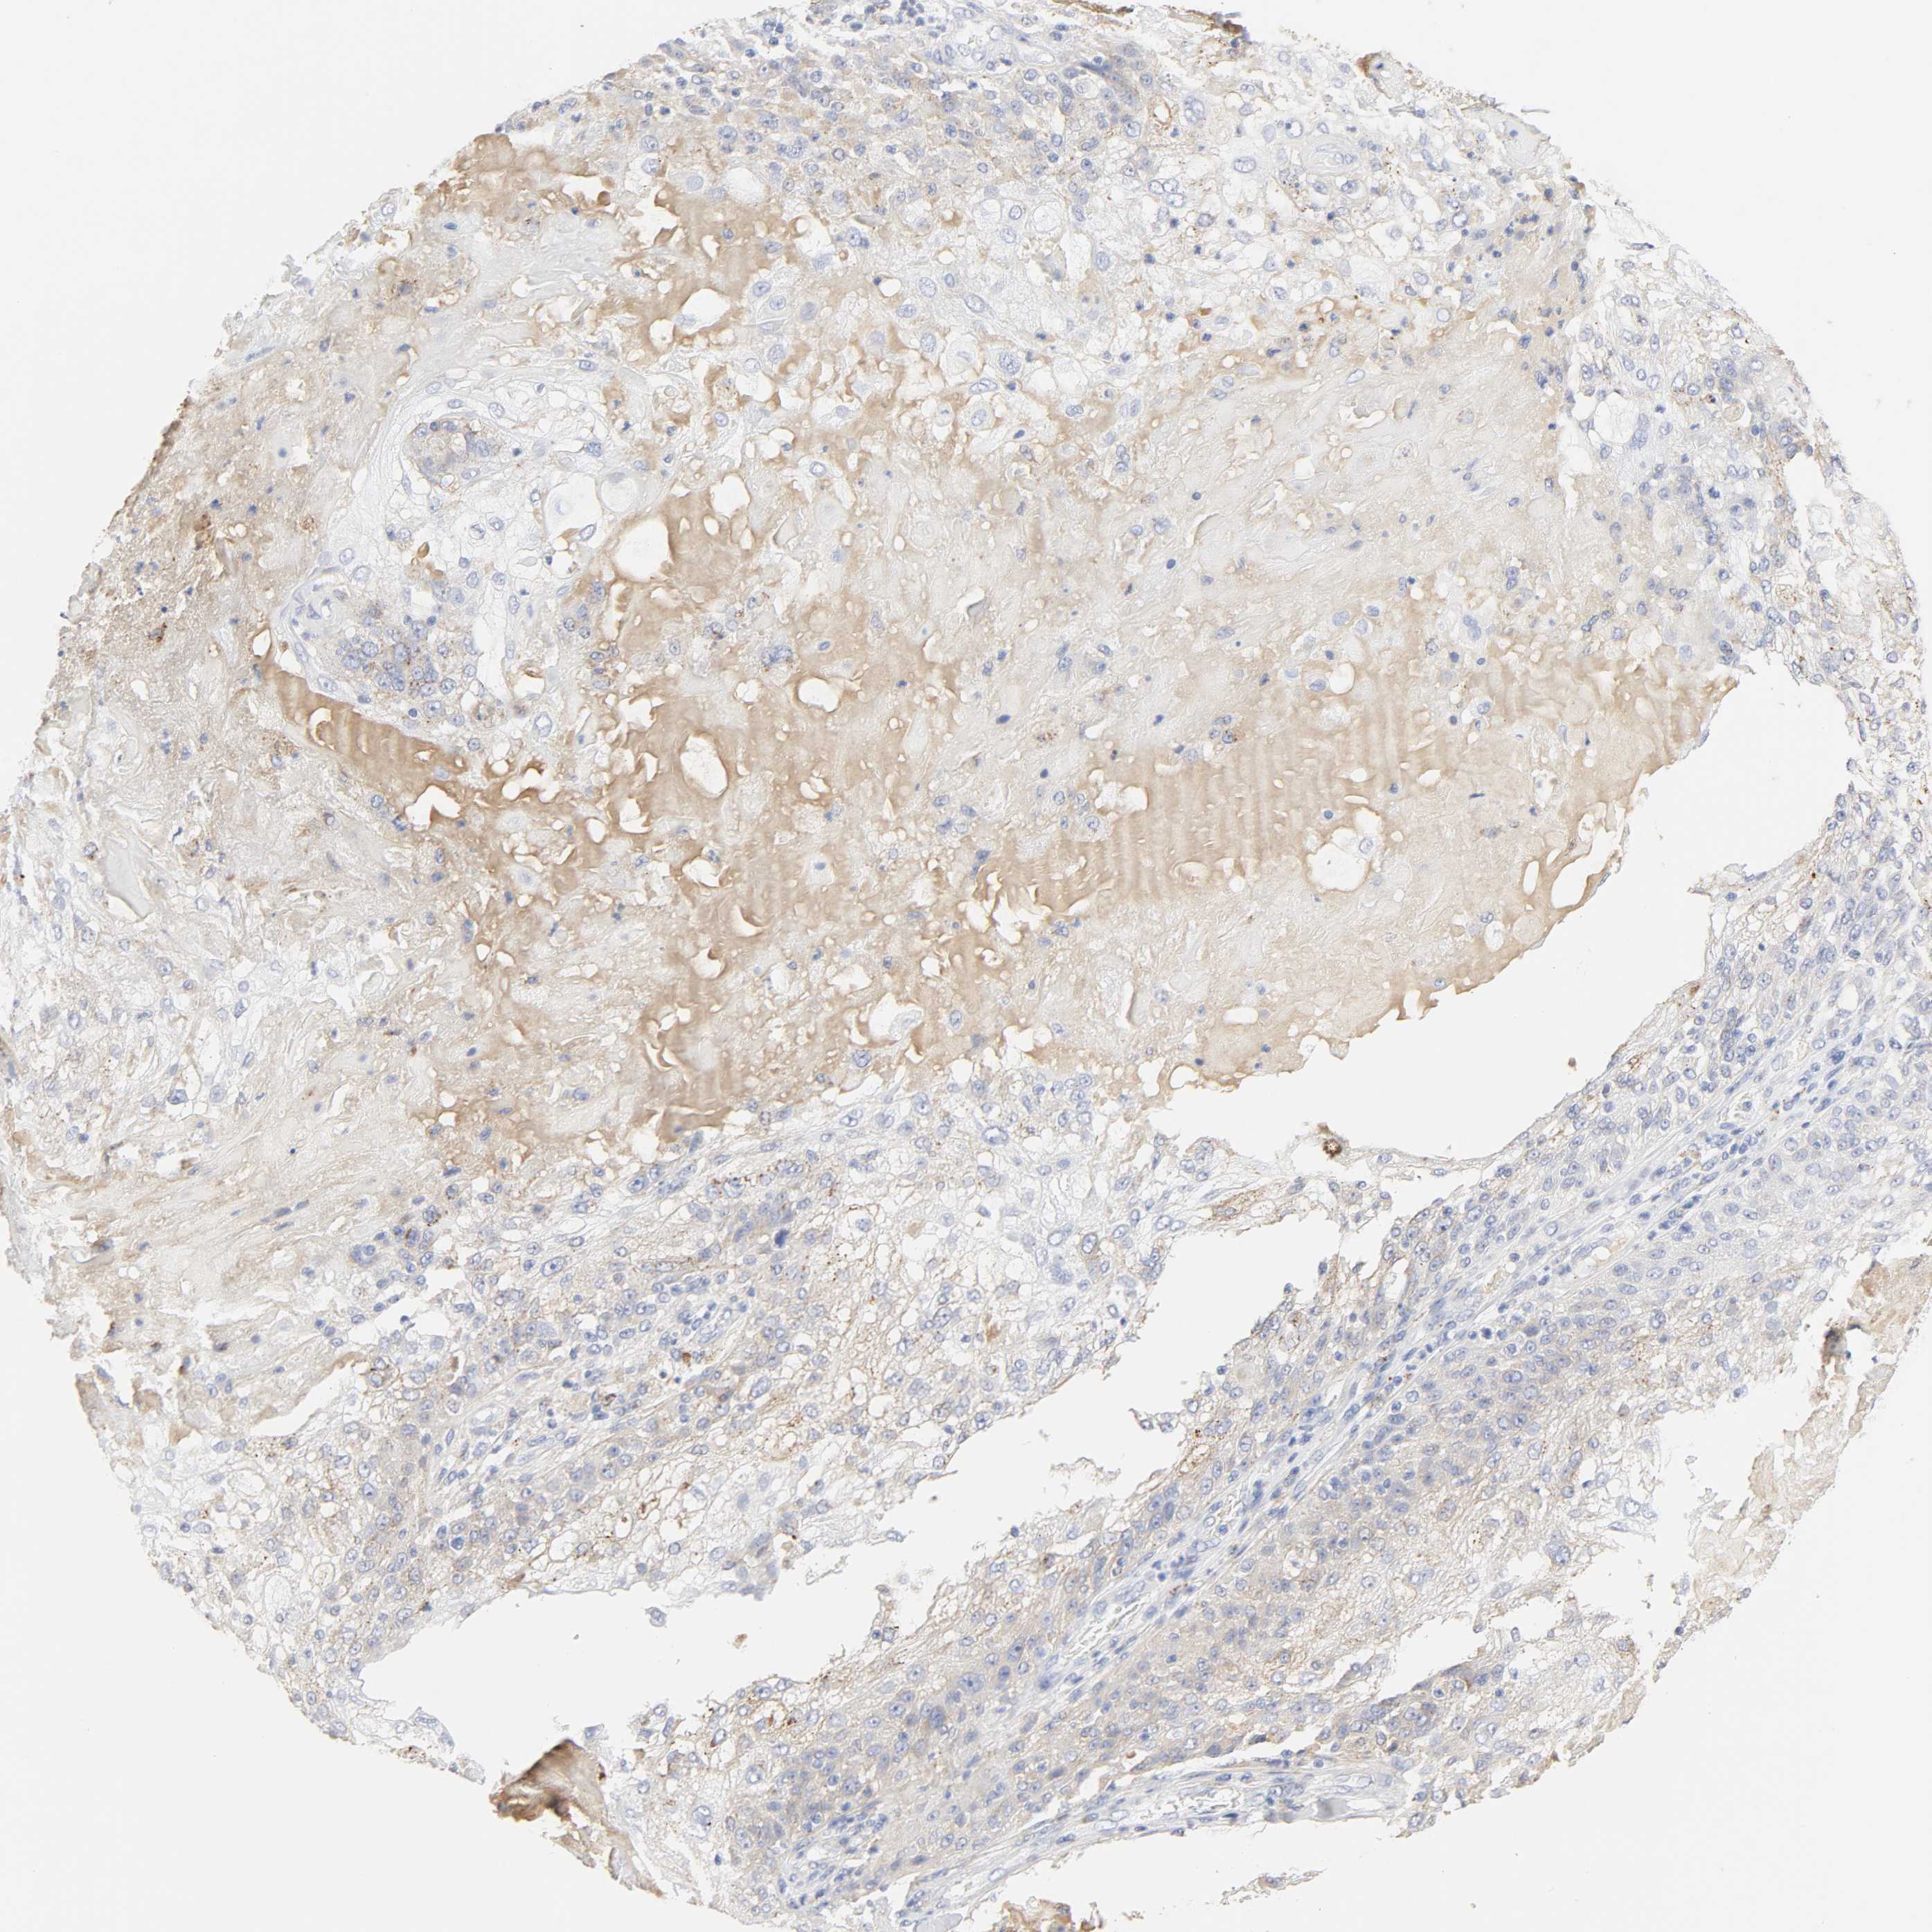

SKIN CANCER - Protein expressioni

A mouse-over function shows sample information and annotation data. Click on an image to view it in a full screen mode. Samples can be filtered based on level of antibody staining by selecting one or several of the following categories: high, medium, low and not detected. The assay and annotation is described here.

Antibody stainingi

Antibody staining in the annotated cell types in the current human tissue is reported as not detected, low, medium, or high, based on conventional immunohistochemistry profiling in selected tissues. This score is based on the combination of the staining intensity and fraction of stained cells.

Each image is clickable and will lead to virtual microscopy that enables deeper exploration of all samples and also displays staining intensity scores, fraction scores and subcellular localization as well as patient and tissue information for each sample.

Antibody HPA003756

Staining

High

Medium

Low

Not detected

Intensity

Strong

Moderate

Weak

Negative

Quantity

>75%

75%-25%

<25%

None

Location

Nuclear

Cytoplasmic/membranous

Cytoplasmic/membranous,nuclear

Squamous cell carcinoma, NOS

Basal cell carcinoma